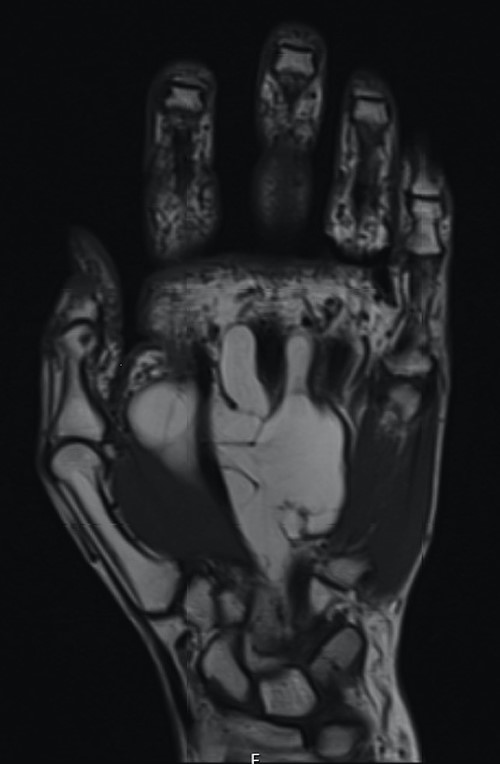

The patient underwent an elective marginal excision under brachial plexus block and tourniquet haemostasis. A volar approach with an extended carpal tunnel release was utilized to access the lesion (Fig. 3). Given the MRI findings of the dorsal extent of the tumour, a dorsal incision was considered and marked pre-operatively. However, this was ultimately not required, as adequate access was achieved using the volar approach to excise the entirety of the lipoma. A multi-lobulated, encapsulated fatty lesion was found in the central palm extending to the carpal tunnel and the dorsal sub-aponeurotic space, involving the third inter-metacarpal space and flexor tendons. The tumour was successfully resected en bloc whilst protecting all tendons and neurovascular structures. The excised lesion measured 12 × 7 × 2.4 cm (Fig. 4). After excision, satisfactory haemostasis was achieved; drain inserted and skin closed using absorbable sutures. No immediate postoperative complications were noted.

Histopathological analysis of the soft-tissue lesion revealed sections showing lobules of mature adipocytes, consistent with a diagnosis of lipoma. There were no features of malignant change. The patient was seen in our hand dressing clinic 3 days postoperatively, whereupon the drain was removed, and wound was noted to be healing well. At the 1-month postoperative review, the patient reported complete resolution of paraesthesia with partial functional recovery including improvement in mobility of all digits and grip strength.